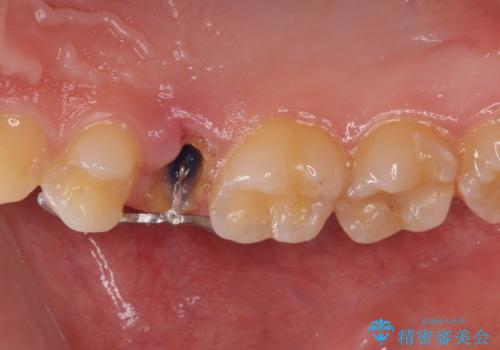

右上の被せものを除去したところ、中で歯が割れていたため、部分矯正で引っ張り出すことになりました。

・両どなりの歯に一時的にワイヤーを接着します。